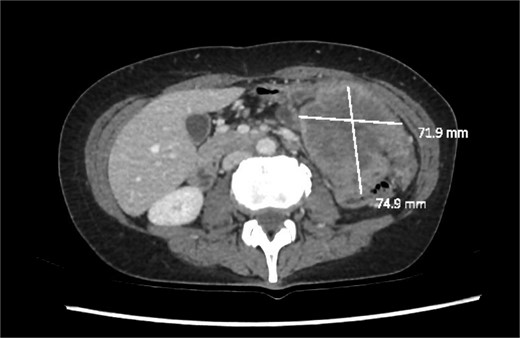

We report a 47-year-old Indigenous woman presenting to a rural centre with nausea, vomiting and abdominal pain. She denied haematochezia or weight loss. Medical history was significant for a previous anterior resection for a T4bN2bM1 (19/44 nodes positive) sigmoid adenocarcinoma ten years prior. The patient received adjuvant chemotherapy with capecitabine at that time, however had poor compliance, did not attend follow up appointments or receive surveillance imaging or colonoscopies. There was no family history of malignancy. There was significant alcohol, tobacco and marijuana use. On examination, she had upper abdominal tenderness without a palpable mass. CEA was 4.6 ug/L, and there was normocytic anaemia. Computed tomography revealed a 7 × 9 × 7cm non-obstructing necrotic splenic flexure mass with adjacent small bowel invasion, however no recurrence at the site of previous anterior resection (Figs 1 and 2). Colonoscopy showed an ulcerated circumferential mass which was unable to be traversed. The patient was transferred to our metropolitan tertiary centre for ongoing management.

Axial slice of a CT demonstrating a large heterogenous mass in the left upper quadrant.